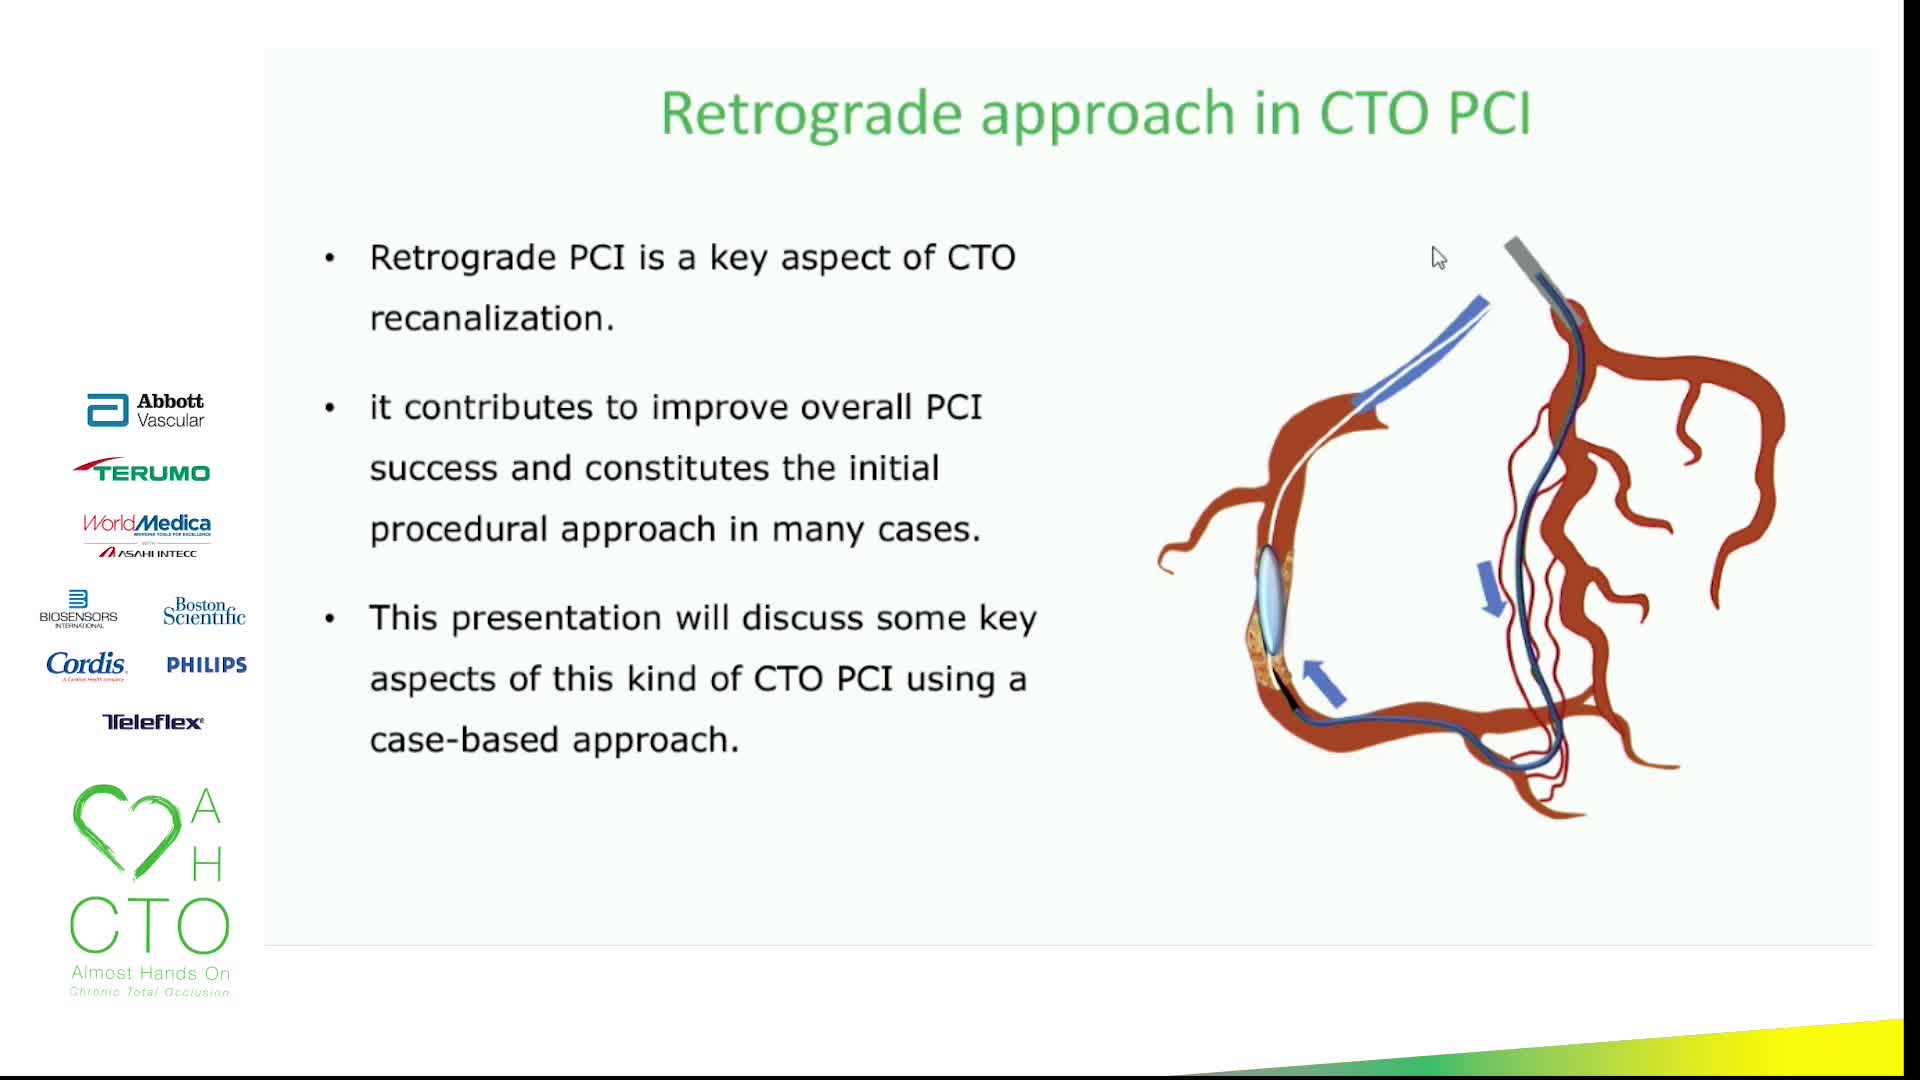

12th AHO meeting December 2020